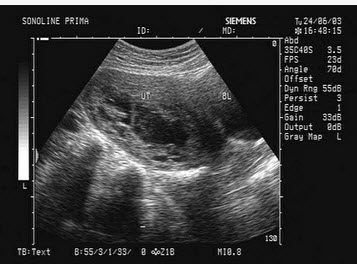

女,26岁,早孕药流后阴道流血就诊,超声声像图如下,最可能的诊断为()

A、正常早孕

B、先兆流产

C、胎盘置入

D、稽留流产

E、不全流产

正确答案:

D